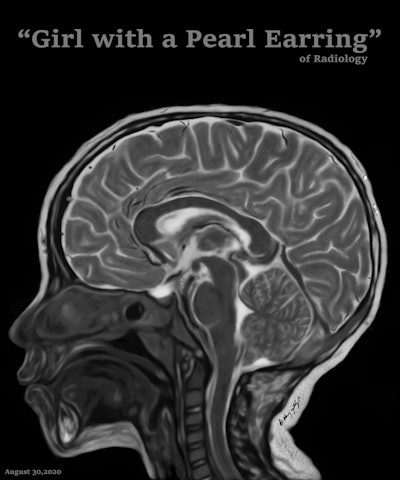

Art and radiology may seem like very different fields, but they can intersect in intriguing ways, particularly in medical imaging and the visualization of complex clinical data. Dr. Harun Yildiz has a keen interest in pediatric radiology, including ultrasound. All images provided by Dr. Harun Yildiz.

Dr. Harun Yildiz has a keen interest in pediatric radiology, including ultrasound. All images provided by Dr. Harun Yildiz.

Dr. Harun Yildiz, a radiologist at Dortcelik Children's Hospital, Bursa, Turkey, is convinced that beauty exists within medical images, and appreciating the aesthetic qualities can boost mental health and help avoid burnout. Ahead of his first lecture about radiological illustrations on 20 November 2025 at 8 p.m. Turkish time/6 p.m. CEST, we asked him to elaborate on his passion for art.

Conceptually, I think it is possible to define the term “radiological illustration” as an emerging discipline that transforms medical imaging data into an aesthetic and didactic narrative. I emphasize that with the motto “pixel by pixel handmade.” I am trying to open a “new path” for the use of visual communication in medical education by trying to combine scientific accuracy in radiological terms with artistic creativity. With this statement, I am trying to express that instead of modifying radiological images, I draw each pixel by hand using technological tools and create a new visual that is both artistically and scientifically original, while remaining faithful to radiological principles.

It’s important to note that radiological illustration should not be confused with medical illustration. The former has yet to be systematically defined in the literature. I believe it deserves recognition as a distinct sub-branch within the broader medical illustration domain.